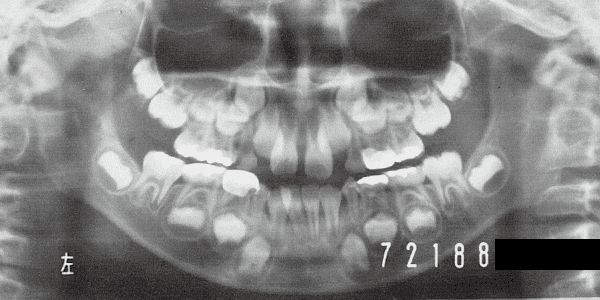

1 At start of treatment 7-21-’88

A case of diverted and cross bite during the deciduous dentition. Despite early treatment, the deviation progressively worsened with age, necessitating surgical treatment. At the initial visit, the patient had a deciduous dentition, and observation was planned (3). With the eruption of the permanent incisors, the mandible shifted slightly to the right, resulting in a cross bite (1) At this point, asymmetry can be confirmed in the front view. However, it is slight. The cephalometric X-ray reveals a structure with a slightly dominant mandible, but asymmetry in the mandibular ramus is not observed.

3 Initial Visit 6-17-’87